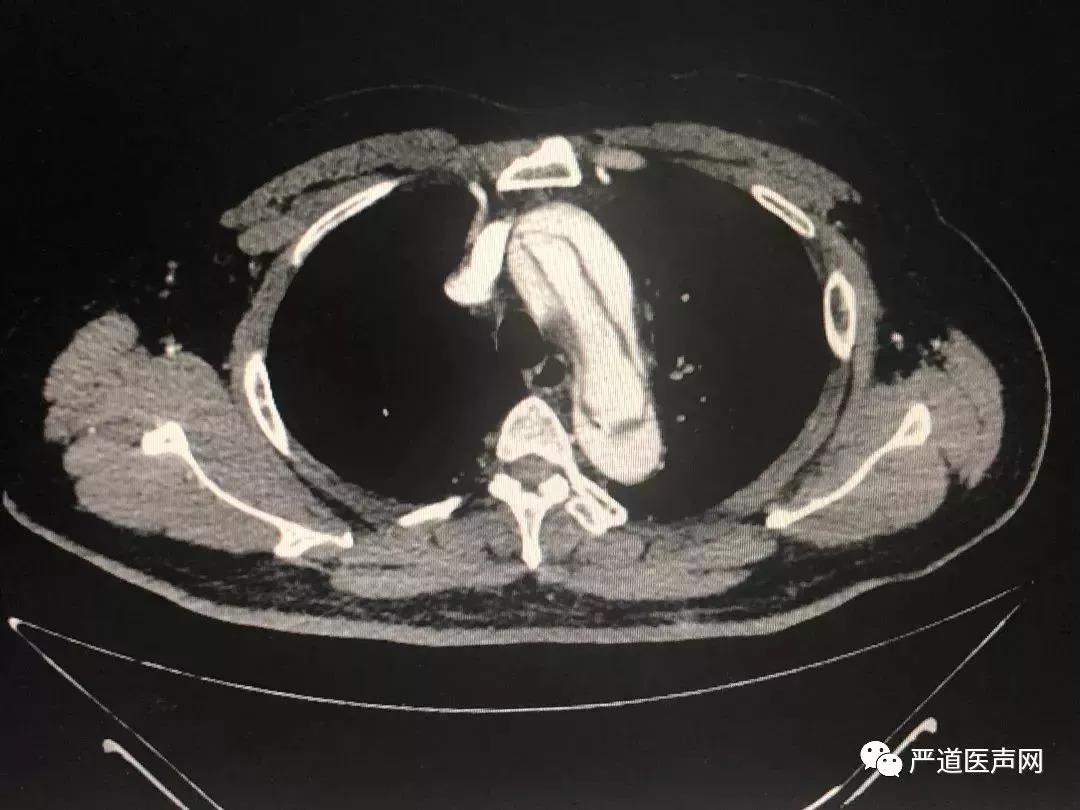

四、冠状动脉CTA检查

考虑到主动脉夹层可能,经猪尾导管行主动脉造影不安全,接下来完成了主动脉CTA检查:

▲主动脉CT提示:自升主动脉根部开始至腹主动脉分出髂动脉之前全段夹层形成

至此,患者胸背痛的原因基本明确:1型主动脉夹层